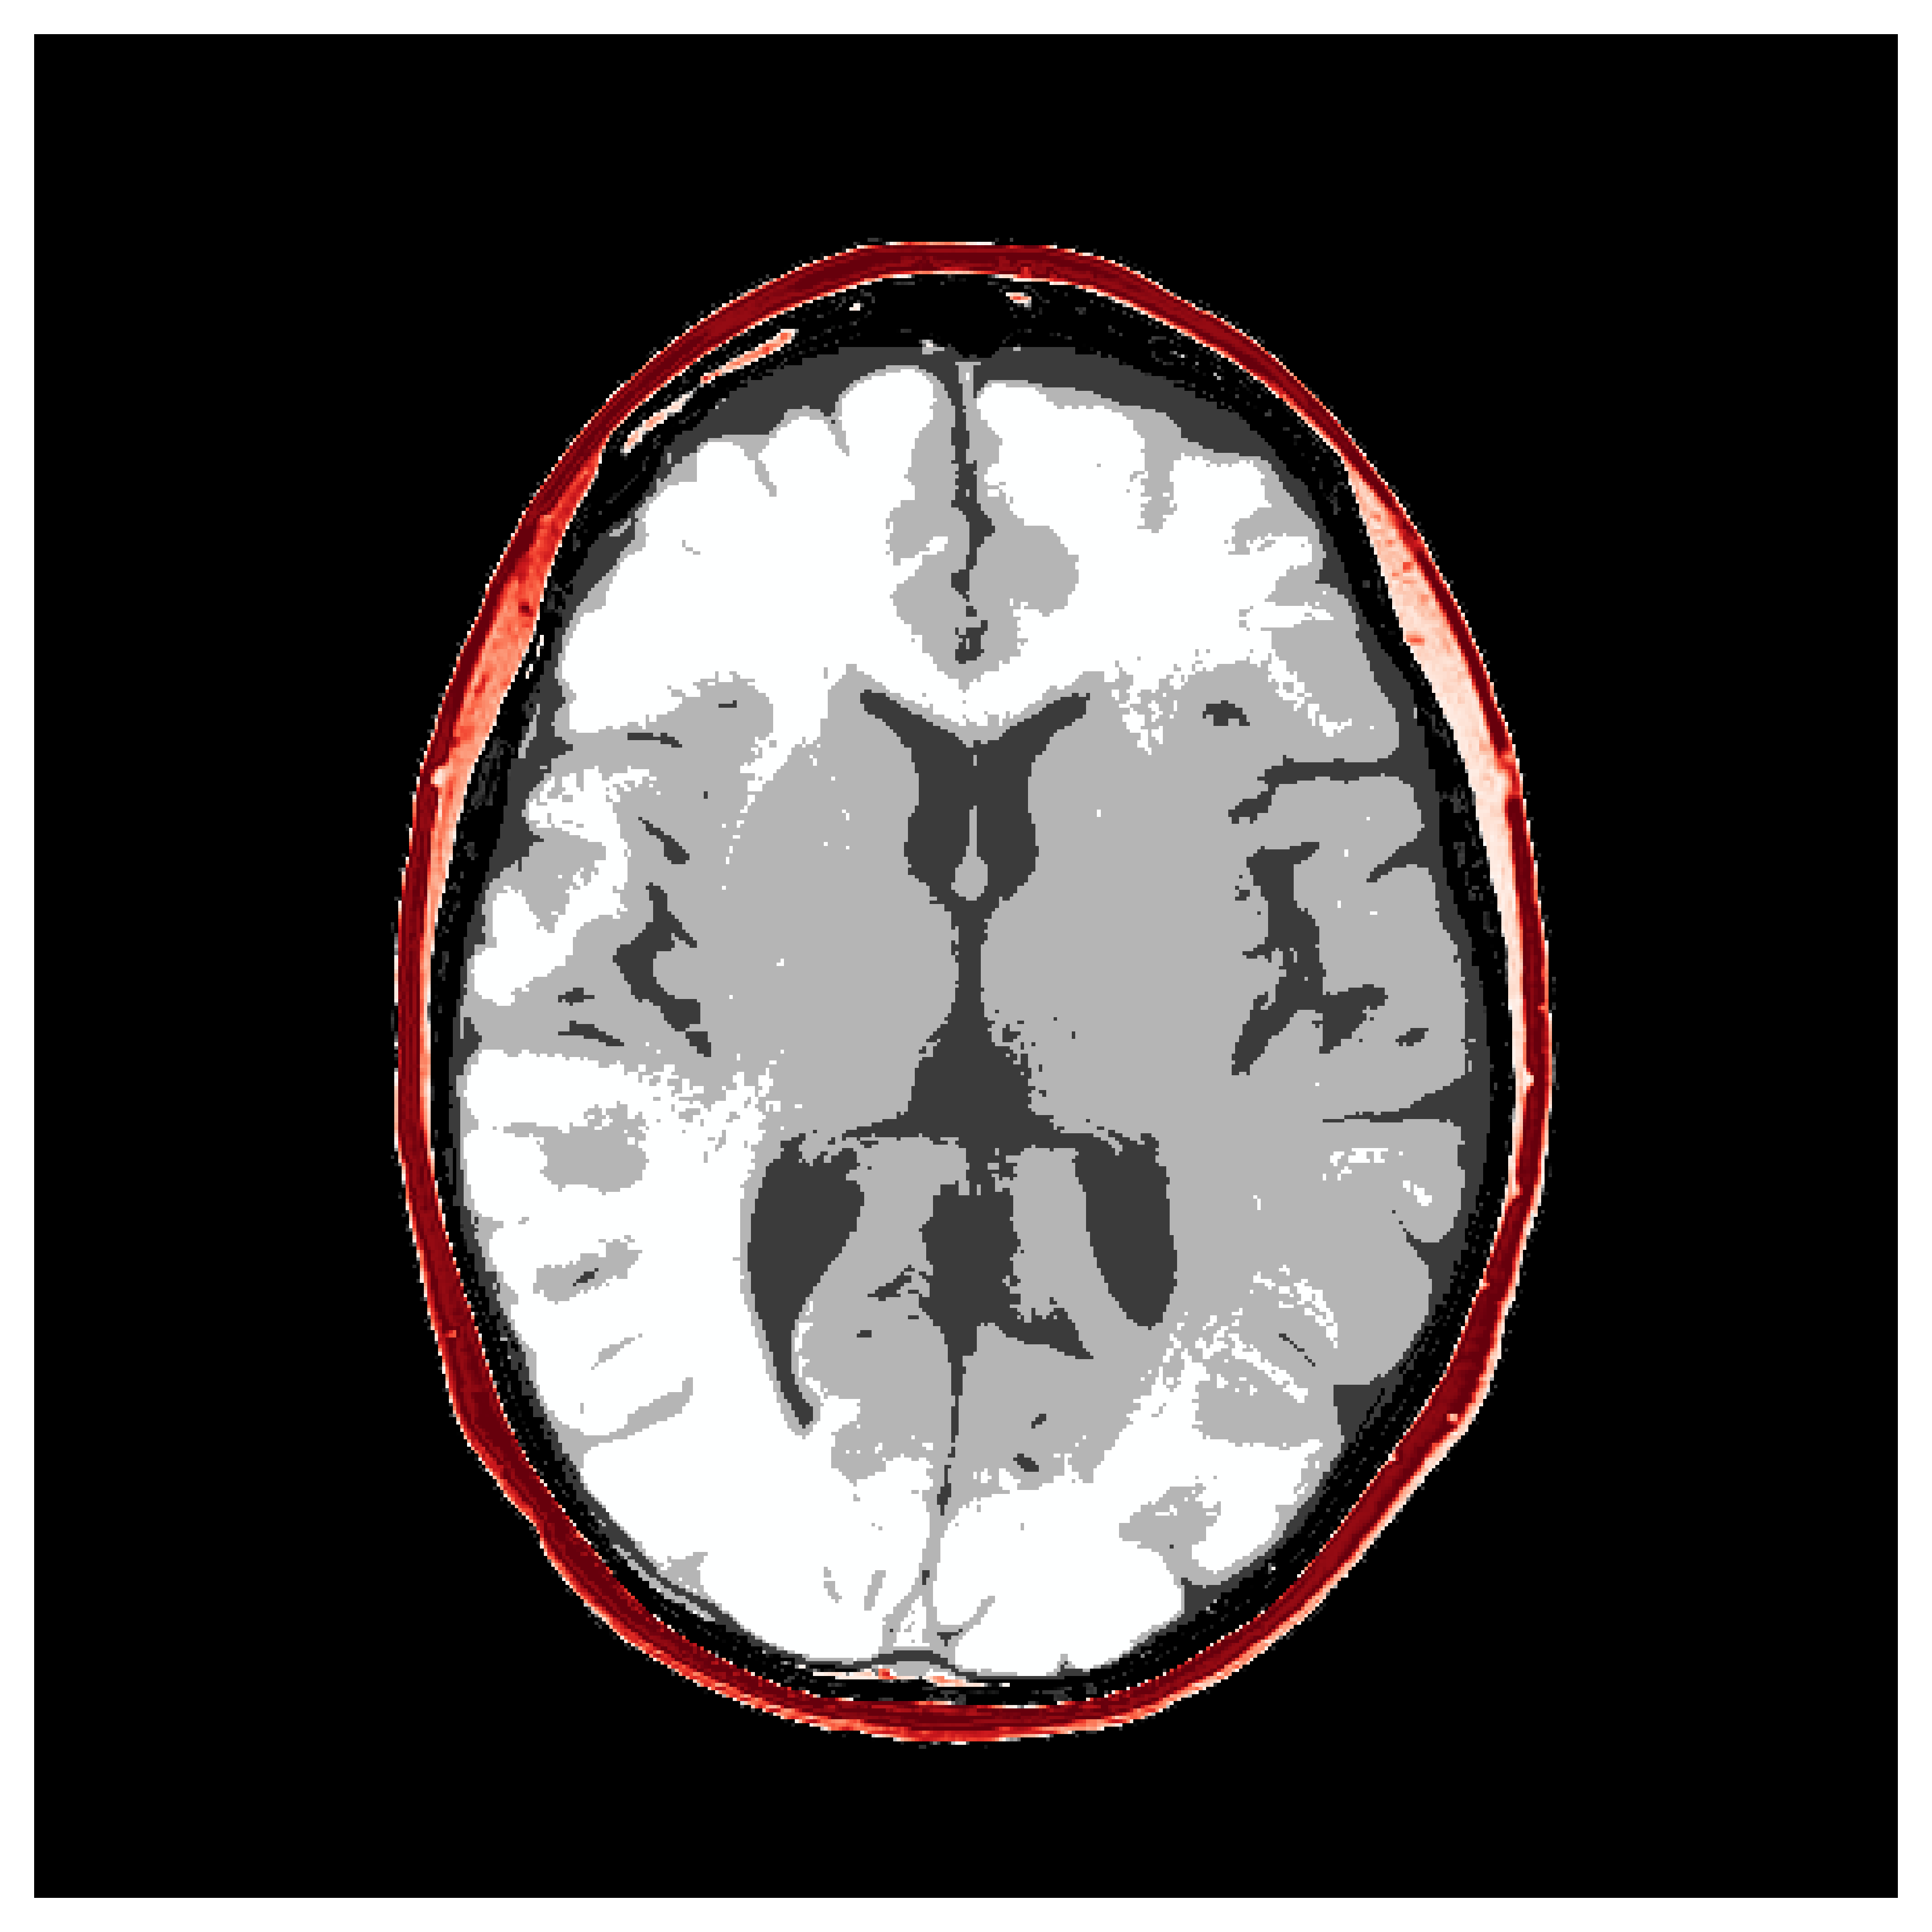

4.2.1 Brain prior samples:

The first step of implementing ASPIRE concerns obtaining samples from a realistic prior for the target parameter vector , in this case, gridded velocity parameters of human brains and skulls. The parameters collected in the MIDA dataset [56] correspond to a single 3D volume for the acoustic velocity collected from a single subject and will unfortunately not be appropriate to train a neural model that will generalize to other human patients. As far as we know, there is no dataset that includes acoustic velocity collected from many patients, so we made our own dataset based off the multi-subject FASTMRI dataset [57]. This custom dataset, detailed in Section \thechapter.A, comprises N=1000 diverse acoustic velocity parameters collected from different human patients, . This size of datasets facilitates generalization of the amortized posterior sampler across different datasets collected from unseen patients. The dataset is accessible via the repo ASPIRE.jl.

Appendix \thechapter.A FASTMRI acoustic dataset creation

Based off of the MRI dataset [57], we manually assigned acoustic values to MRI intensities by following the table of acoustic brain tissue properties in the supplemental section of [47]. Although MRI intensities are not necessarily related to acoustic tissue properties, we found that we could produce reasonably realistic acoustic parameters as compared to the acoustic parameters from the MIDA volume. In Figure 19, we show some example training acoustic parameters. We also plot the average and standard variation between all 1000 training samples in Figure 20. From these plots, we note that there are few similarities between training examples apart from the biologically consistent human brain structures.